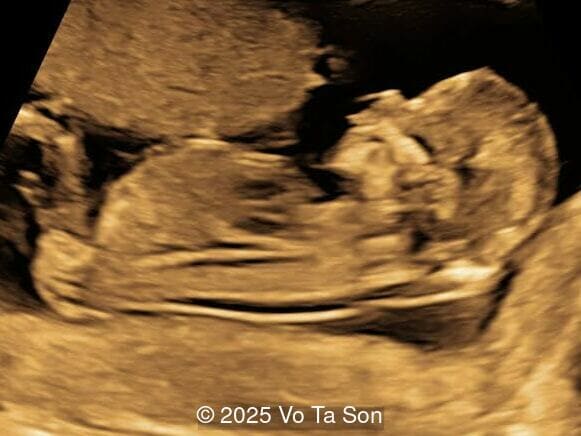

A woman underwent routine prenatal screening at 13 weeks. The non-invasive prenatal test (NIPT) showed low risk for common aneuploidies including trisomy 21, 18, and 13. However, first-trimester anomaly scan revealed multiple fetal anomalies.

Please describe the abnormalities and provide a syndromic diagnosis that best fits the presentation.